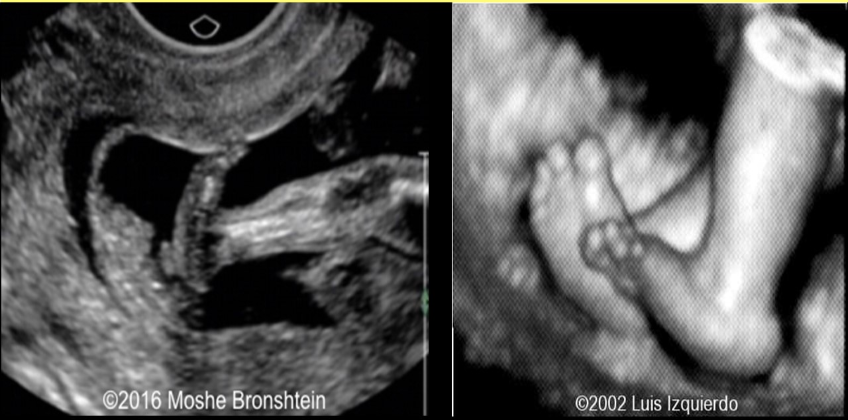

what pedal abn is assoc w/trisomy 13 + 18

a) talipes equinovarus

b) polydactyly

c) club foot

d) rocker bottom foot